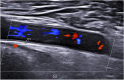

Methods: We included 44 patients with LV-GCA and 42 with high-risk atherosclerosis. US examinations of the axillary, subclavian, and common carotid arteries (CCA) were systematically performed using a MylabX8 system (Genoa, Italy) with a 4-15-MHz probe. IMT ≥ 1 mm was accepted as pathological.

Results: The LV-GCA cohort included 24 females and 20 males with a mean age of 72.8 ± 7.6 years. The atherosclerosis group included 25 males and 17 females with a mean age of 70.8 ± 6.5 years. The mean IMT values of all arteries included were significantly higher in LV-GCA than in atherosclerosis. Among LV-GCA patients, IMT ≥ 1 mm was seen in 31 axillary, 30 subclavian, and 28 CCA. In the atherosclerotic cohort, 17 (38.6%) had IMT ≥ 1 mm with axillary involvement in 2 patients, subclavian in 3 patients, carotid distal in 14 patients (5 bilateral), and isolated carotid proximal affectation in 1 case. A cutoff point greater than 1 pathological vessel in the summative count of axillary and subclavian arteries or at least 3 vessels in the count of six vessels, including CCA, showed a precision upper 95% for GCA diagnosis.

Conclusion: The IMT is higher in LV-GCA than in atherosclerosis. The proposed US halo count achieves an accuracy of > 95% for the differential diagnosis between LV-GCA and atherosclerosis. The axillary and subclavian arteries have higher discriminatory power, while carotid involvement is less specific in the differential diagnosis.